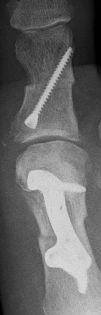

...Nasenscheidewand am 14.11.2013 und beide großen Zehen am 11.12.2013 - abwechlungsreich ist es aber.